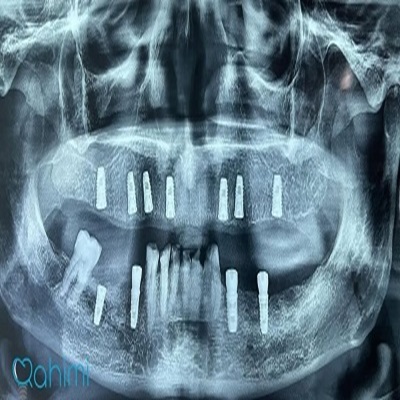

دکتر حامد رحیمی

دکتر حامد رحیمی متولد سال ۱۳۶۷ می باشند.ایشان در سال ۱۳۸۵ موفق به ورود به رشته دندانپزشکی دانشگاه علوم پزشکی تهران شدند و در سال ۱۳۹۱ فارغ التحصیل گردیدند.در سال ۱۳۹۴ پس از گذراندن طرح دوره دکتری عمومی در استان قم موفق به قبولی در رشته جراحی لثه و ایمپلنت دانشکاه علوم پزشکی تهران گردیدند.ایشان از سال ۱۳۹۷ و پس از کسب بورد تخصصی به عنوان عضو هیات علمی دانشگاه علوم پزشکی قم مشغول هستند.